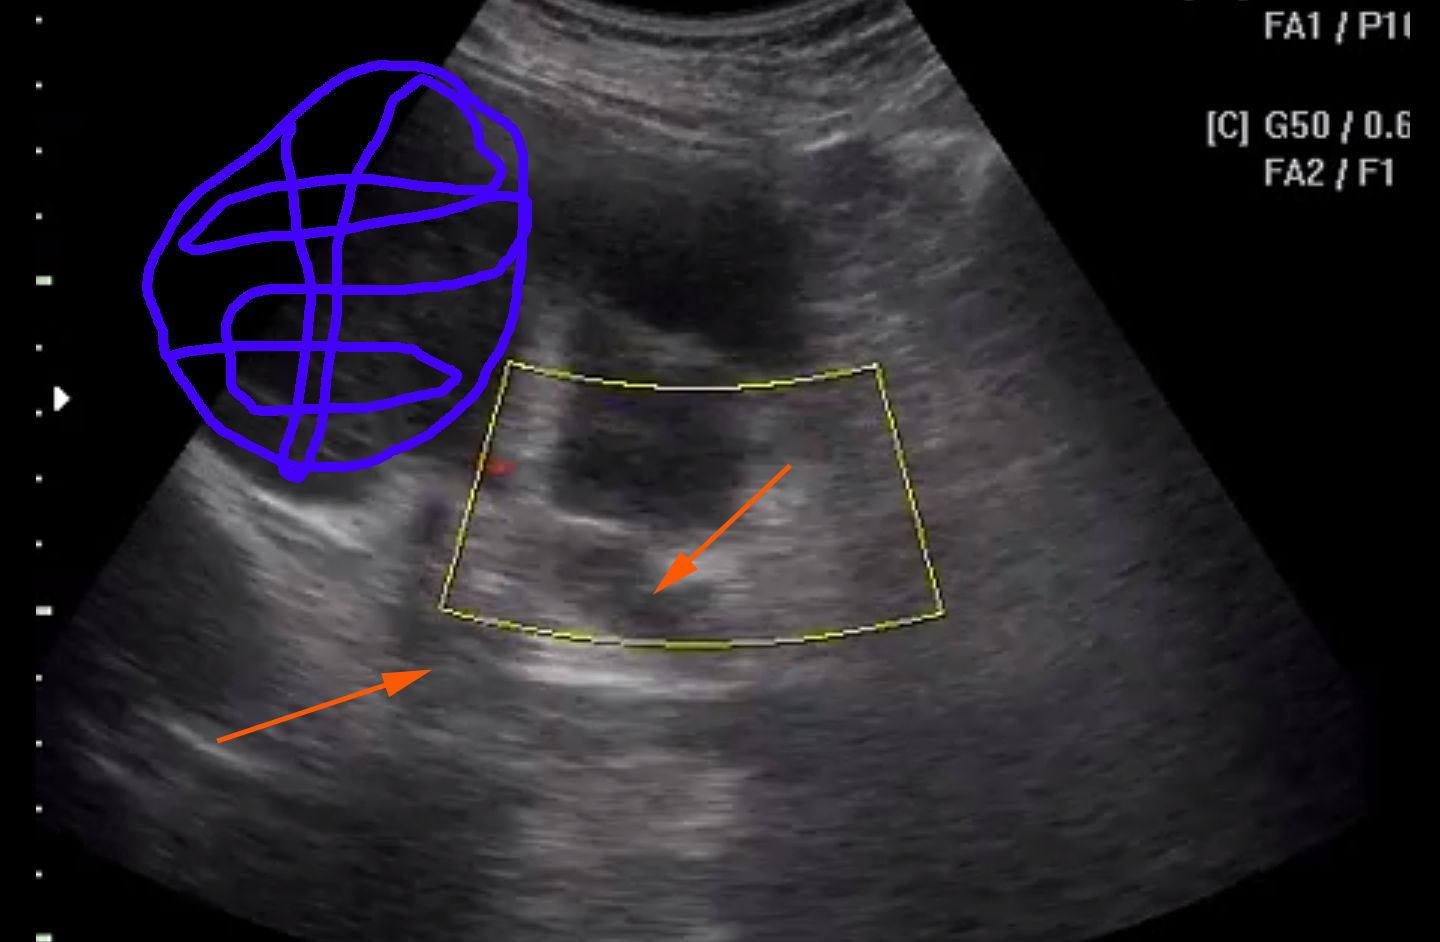

Вот здесь видно

Слева <-- видна опухоль (синий цвет в снэпшоте внизу), а справа -> почка со угадываемыми очертаниями.

из последнего клипа

Красная стрелка - сосуд или сосуды, тумор - синий цвет.